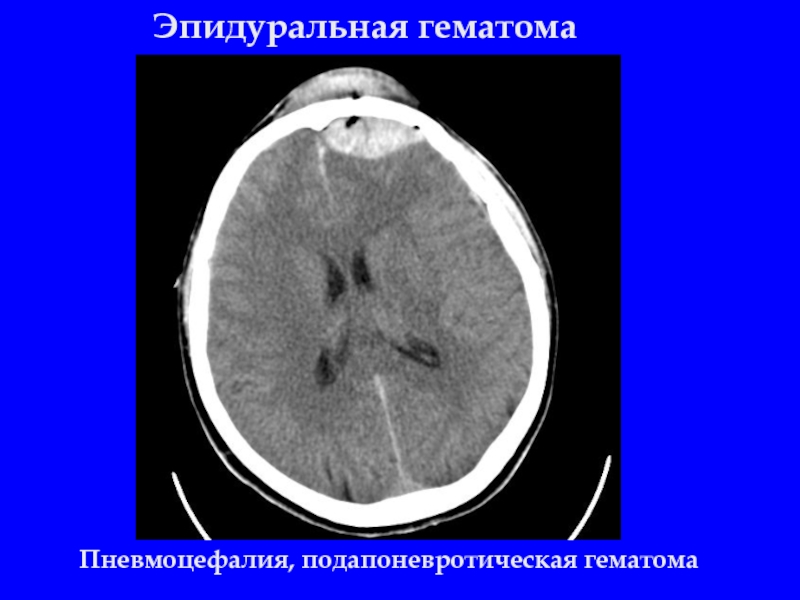

Слайд 12Эпидуральная гематома

Пневмоцефалия, подапоневротическая гематома